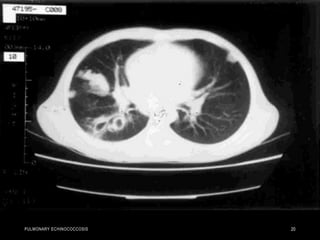

• Air penetrating the

interior of the cyst may

outline the inner surface

producing parallel

arches of air that are

referred to as Cumbo

sign with an "onionpeel“

appearance .